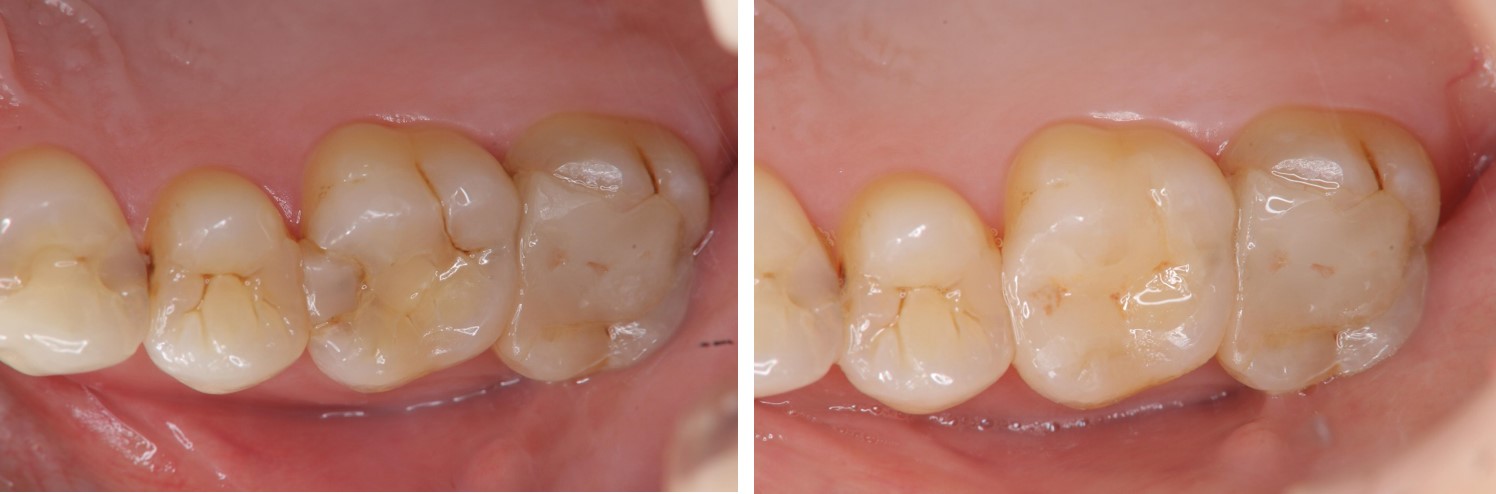

術前、術後比較

當蛀牙破壞程度大,陶瓷崁體是根據蛀牙的窩洞量身訂做,不管是顏色、精密度都是最佳的選擇,因此是非常美觀與持久的填補窩洞材料與技術。